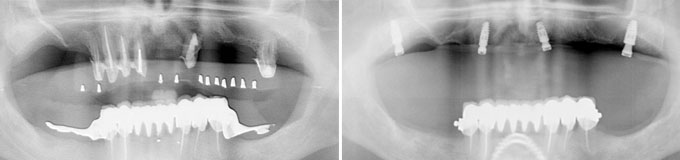

Il me manque de nombreuses dents, les autres sont perdues, je veux l’idéal.

Solution : on peut remplacer toutes vos racines manquantes ou perdues par autant de racines artificielles et vous redonner des dents fixes partout.

Toutes dents sont hélas perdues. Toutes les dents absentes sont remplacées par des couronnes sur implants.